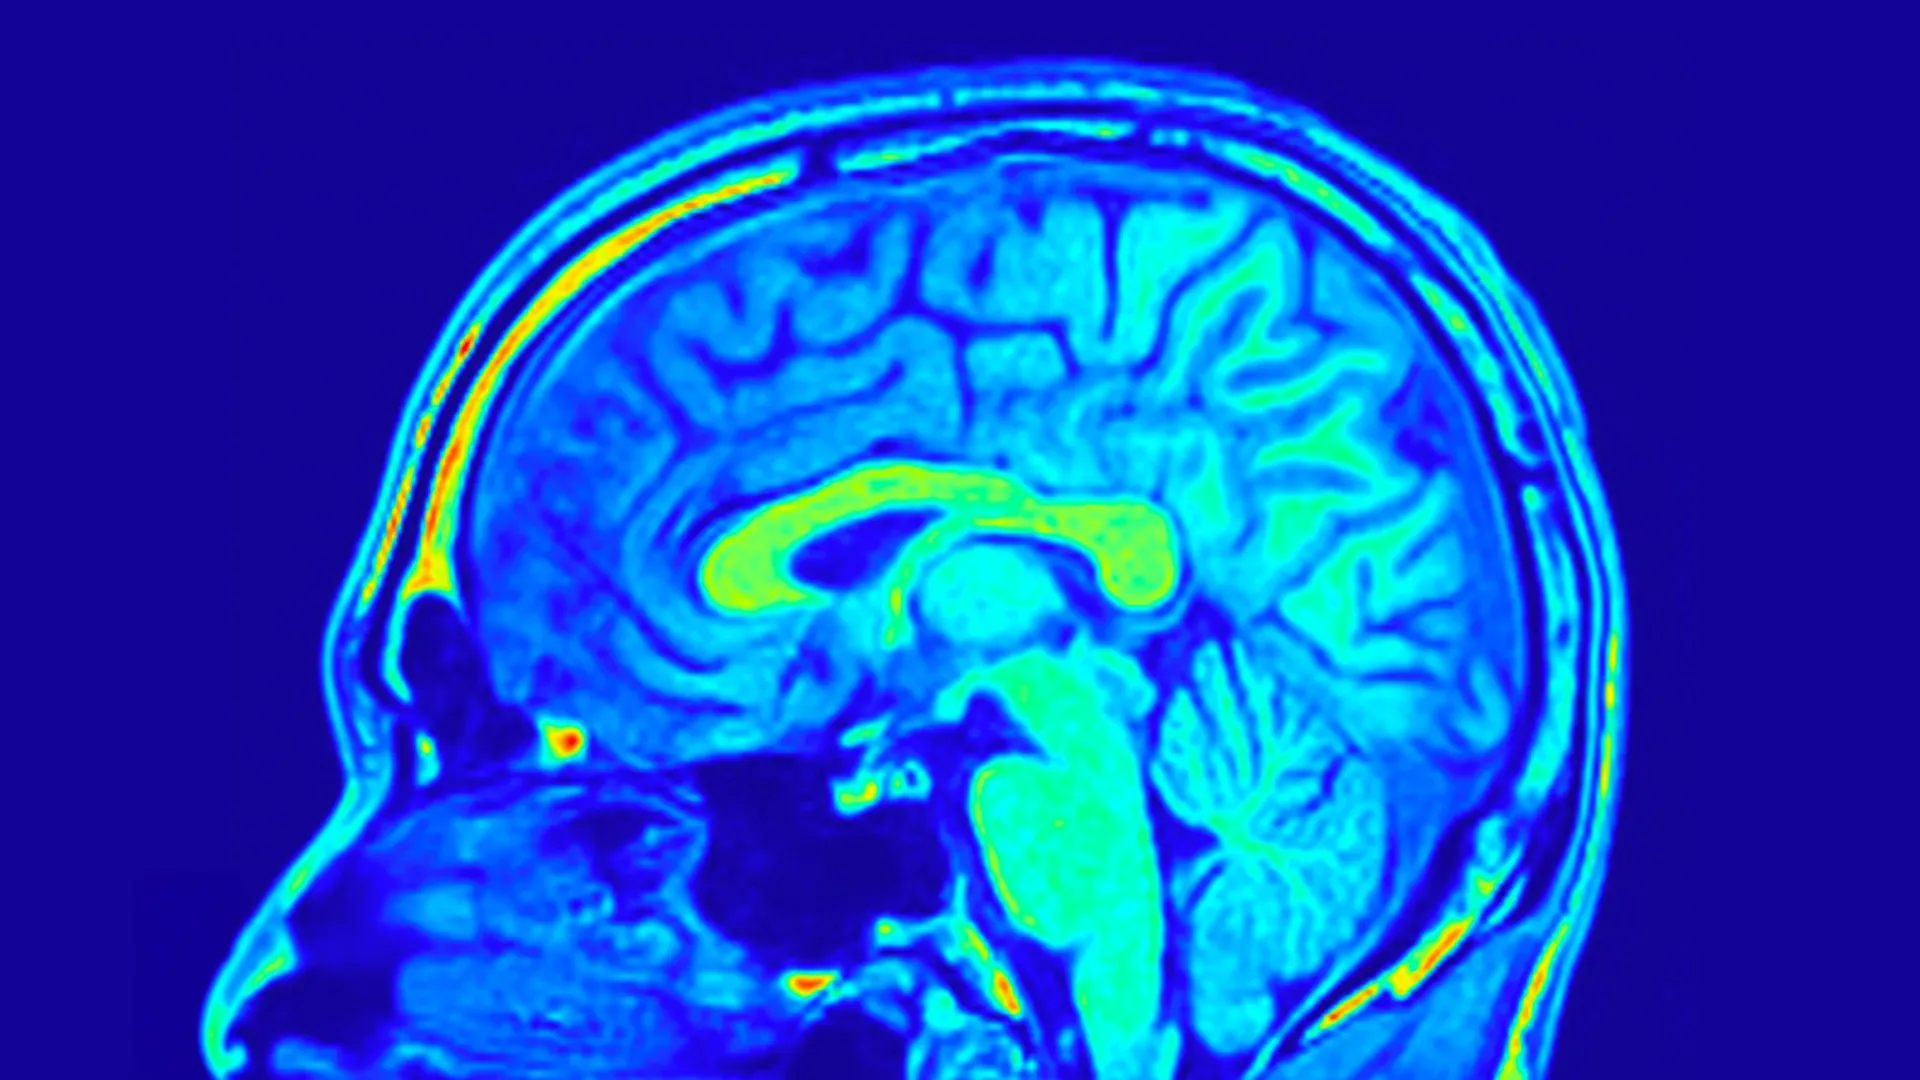

To comprehensively assess treatment effectiveness, the research team employed a multi-faceted approach. The severity of depressive symptoms was quantitatively measured using the Hamilton Depression Rating Scale (HAMD-24), a widely adopted and validated clinical assessment tool. Beyond subjective symptom reporting, the study incorporated objective biological assessments. Peripheral blood samples were collected to analyze specific biochemical markers, and advanced magnetic resonance imaging (MRI) brain scans were performed to meticulously examine alterations in brain structure and underlying biological processes.

The insights gleaned from the brain imaging data provided an even more granular understanding of treatment effects. The researchers identified specific neural networks, formed by the intricate interconnections of various brain structures, that exhibited a predictive capacity for changes in depression scores across both treatment arms. These neural networks represent the functional organization and communication pathways within the brain.

More remarkably, a distinct set of brain structural patterns emerged as being predictive of treatment response exclusively in patients who received Yueju Pill. These predictive patterns were characterized by quantitative measures of sulcal depth and cortical thickness, which describe the complex folding of the cerebral cortex and the thickness of its outermost layer, respectively. Both sulcal depth and cortical thickness are fundamental neuroanatomical features intimately associated with brain development, plasticity, and overall cognitive function. Further in-depth analysis illuminated the significant role of the brain’s visual network in predicting improvements in depressive symptoms and, importantly, in correlating with the observed increases in BDNF levels among individuals treated with Yueju Pill. This suggests a potential pathway through which the herbal intervention might exert its beneficial effects, possibly influencing mood regulation via modulations in visual processing pathways.